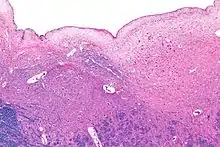

صورة مجهريّة للقسم الخلفي من الجزء المفتوح من النخاع المستطيل، تُظهر البطين الرابع (في قمة الصورة) و نواة العصب تحت اللسان (في الوسط و اليسار) و النواة المحركة الظهرية للعصب المبهم (الوحشي و اليمين).